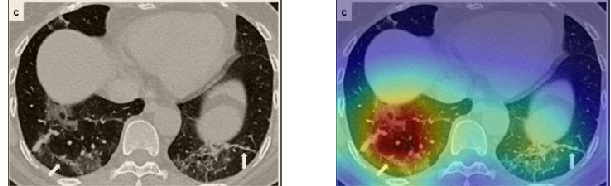

In order to make our models more transparent and provide detailed visual analysis, we present the Grad-CAM localization maps obtained by different models. We consider CT images with COVID-19 abnormalities from the test set of each dataset and highlight the important regions considered for the prediction. For the SARS-CoV-2 dataset we use the Inception V3 model. Figure 13 shows the original CT images and their localization maps. Our model is capable to detect regions that show abnormalities in the CT scans.

A wide variety of typical and atypical CT abnormalities have been reported for COVID-19 patients in various studies [58, 59]. So, we tested our models on external CT images extracted from these two publications as they feature typical findings of COVID-19 pneumonia marked by specialists. In order to make sure that not any of the extracted images are unintentionally included in our datasets, specifically the COVID19-CT dataset, we use the model trained on the SARS-CoV-2 dataset. First, the InceptionV3 model is employed to classify the extracted CT images. The model is able to correctly classify the given CT images as COVID-19. Second, in order to interpret the model’s generalization capabilities, we apply the Grad-CAM technique to visualize the regions of abnormalities that are considered. By assessing the different CT images in Figure 15, we can see that the model accurately localizes the disease-related regions. Even more interesting is the fact that the model ignores any specific marks in the images like letters and only localizes the COVID-19 related regions. These visual explanations show the success of our models to learn relevant, generic visual features related to COVID-19 and are capable to correctly classify CT images outside the datasets on which they are trained.